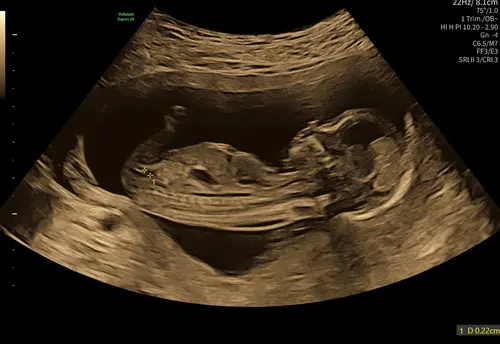

Wat denken jullie aan de hand van bovenste foto 🥹

Ik denk meisje